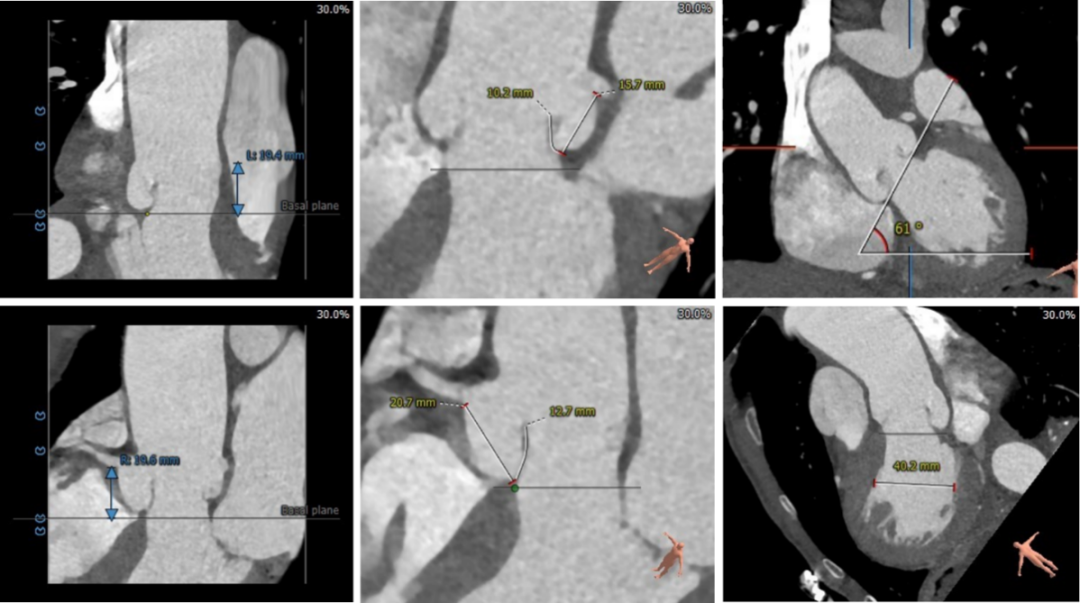

术前CT评估

▪ 三叶式主动脉瓣,微量钙化,瓣叶稍增厚。

▪ 左右冠高度可,左右冠瓣长度小于冠脉开口与瓣叶附着缘距离。

▪ 左室流出道呈直筒型,瓣环下4cm流出道内径约26mm,瓣环下5mm内径约27.5mm,稍大于瓣环内径。瓦氏窦较宽,窦管交界及升主动脉内径可,升主动脉无扩张。

▪ 左室腔内径可,心室壁无增厚。

▪ 主动脉瓣环与水平面夹角较大61°,横位心,主动脉弓角度较锐利76°,弓距良好。

▪ 入路血管散在钙化,局部较严重,双侧血管内径良好,整体入路血管条件良好。

主动脉根部测量及钙化评估

冠脉阻挡风险评估

外周血管入路评估